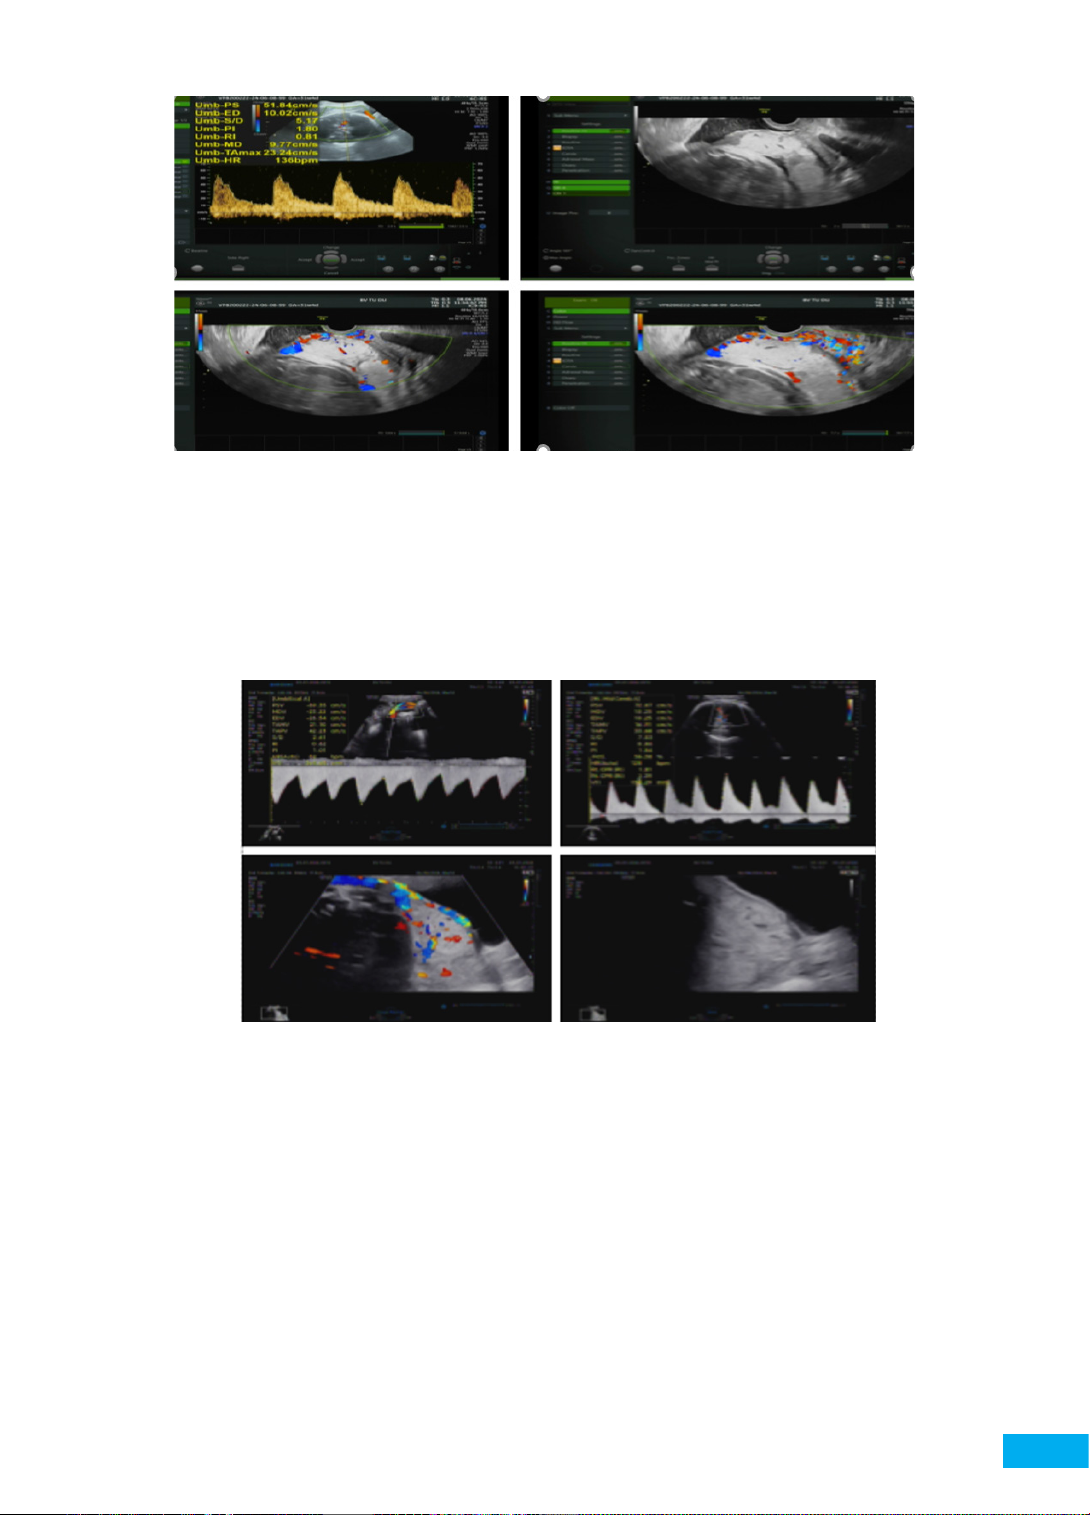

Lúc thai 15 - 16 tuần, siêu âm (Hình 3) thấy chiều

dài kênh cổ tử cung ngắn 21 mm, nhau tiền đạo, nghi

ngờ có phổ nhau cài răng lược. Bệnh nhân không đau

bụng, không gò tử cung. Khám cổ tử cung đóng, âm đạo

không huyết. Chúng tôi tư vấn nguy cơ sinh non và các

phương pháp dự phòng, sản phụ mong muốn được đặt

vòng nâng cổ tử cung dự phòng sinh non. Sau khi xem

xét kỹ các yếu tố nguy cơ, bệnh nhân được chỉ định đặt

vòng nâng Arabin ASQ70/21/32 (con rạ, đơn thai, CTC

đóng) đồng thời sử dụng thuốc nội tiết progesterone 400

mg/ngày đặt âm đạo.

Hình 3. Chiều dài kênh cổ tử cung ngắn 21 mm, hình ảnh bánh nhau lúc 15 - 16 tuần.

Nhau mặt sau, mép dưới bánh nhau tràn qua lỗ trong cổ tử cung lan ra mặt trước, hình ảnh bánh nhau

không đồng nhất, có nhiều xoang mạch máu đa hình dạng trong bánh nhau (dấu Lacunae).

Có hình ảnh giàu mạch máu ở đoạn dưới, vị trí tiếp xúc với thành bàng quang.

Hình 4. Siêu âm lúc thai 31 tuần 4 ngày, nhau tiền đạo, NCRL percreta.

(Có 03 xoang mạch máu đa hình dạng trong bánh nhau, mất đường echo kém ranh giới giữa bánh nhau

và tử cung, mất cơ tử cung vùng vết mô. Các xoang mạch máu trong bánh nhau có hiện tượng bắt màu trung bình,

tăng sinh mạch máu trung bình mặt phân cách nhau - tử cung, có thể có xâm lấn bàng quang,

không xâm lấn vách chậu - cổ tử cung)

Percreta (Hình 5).

Hình 5. Siêu âm lúc thai 35 tuần, nhau tiền đạo, NCRL percreta.

(Nhau mặt sau bên phải nhóm 3, bờ dưới bánh nhau tràn qua lỗ trong CTC, có hình ảnh bánh nhau phồng lên,

có > 3 xoang mạch máu đa hình dạng trong bánh nhau, mất đường echo kém ranh giới giữa bánh nhau và tử

cung, mất cơ tử cung vùng vết mô. Tăng sinh mạch máu nhiều mặt phân cách nhau - tử cung,

có xâm lấn bàng quang, không xâm lấn vách chậu - cổ tử cung)